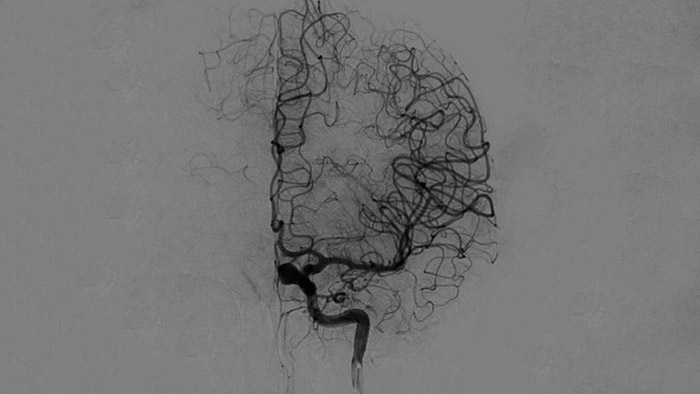

Технология ClarityIQ применяет опцию автоматической компенсации артефактов движения во время проведения DSA в режиме реального времени, чтобы создавать четкие изображения сосудов. Это способствует принятию верных решений во время операций по лечению инсульта.

Высококачественная визуализация в режиме DSA позволяет оценить, был ли тромб полностью удален и произошло ли растворение сгустков крови в головном мозге. Врачам предоставляется возможность проверить восстановление кровотока в области ишемической полутени, а также наличие кровотечений в периоперационный период.

Принимайте обоснованные решения о том, можно ли добраться до сгустка и какой путь использовать. Технология Roadmap Pro, усовершенствованная схема сосудов с двойным контрастом, помогает улучшить визуализацию перекрывающихся сосудов, сохраняя при этом баланс дозовой нагрузки.